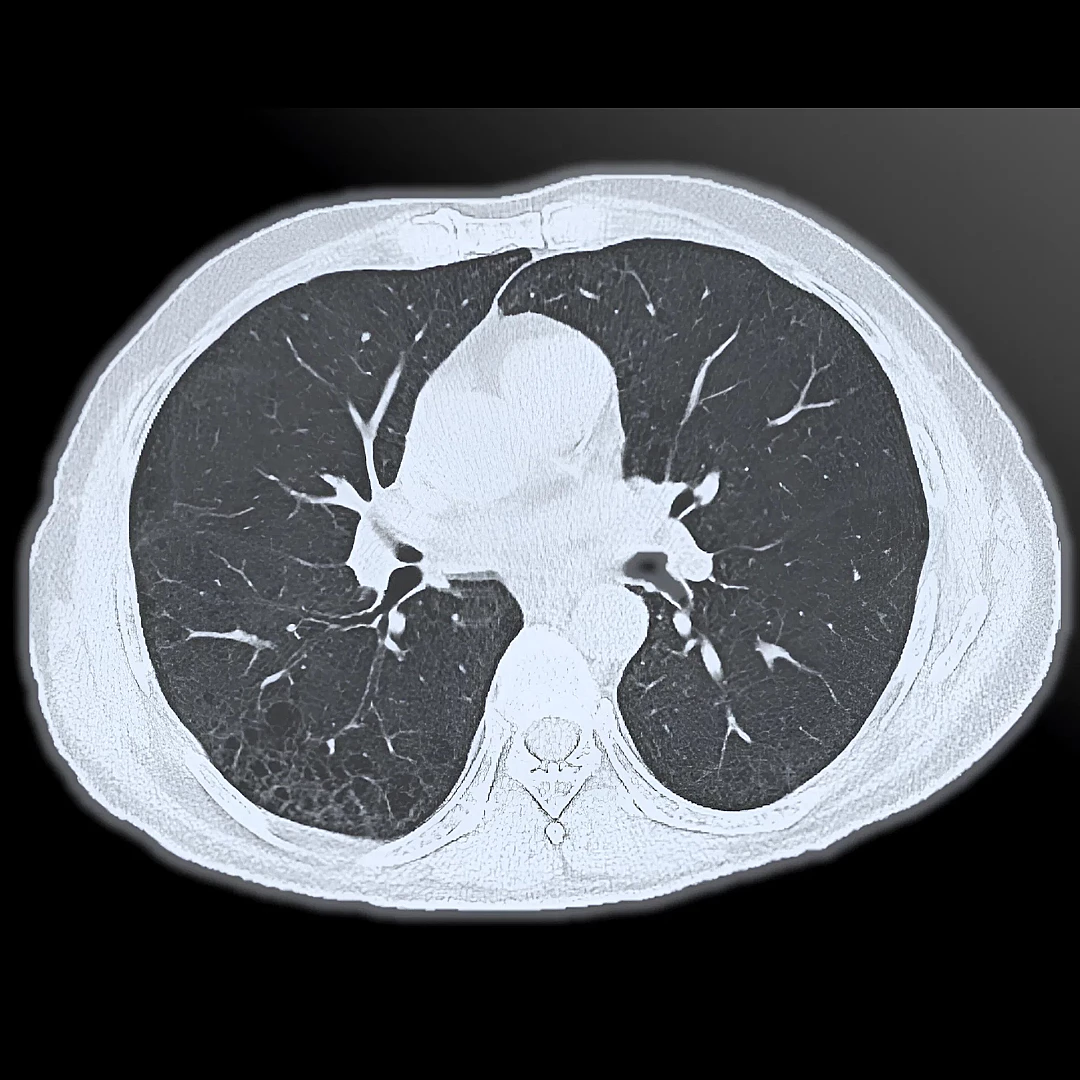

Standard & High-Resolution Chest CT

Standard and High-Resolution Chest CT provides detailed imaging of the lungs, airways, and chest structures to detect infections, tumors, or interstitial lung disease. High-resolution scans offer greater clarity for assessing subtle lung abnormalities with precision.